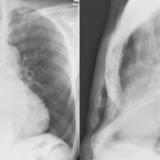

Giant RA PALat

Date: 01/07/2012

Views: 2530